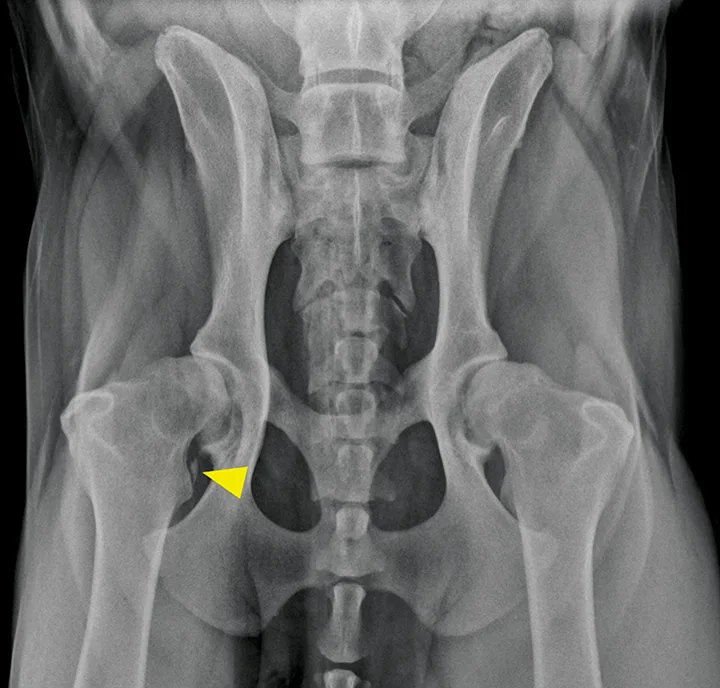

FIGURE 5

Ventrodorsal radiographic projection of a 9-year-old dog with right hindlimb lameness and hip pain. In addition to bilateral hip dysplasia and secondary osteoarthritis, mineralization is present within the right iliopsoas muscle near the tendon insertion on the lesser trochanter (arrowhead), which indicates a chronic strain injury.